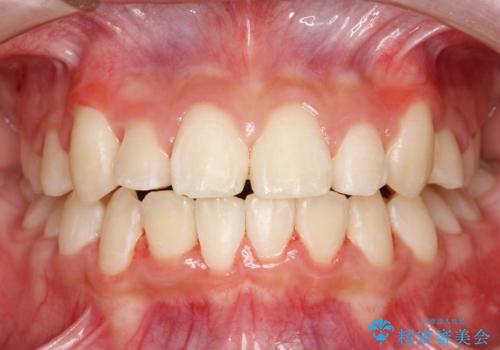

乳歯・過剰歯を除去し、リンガルアーチを用いて埋伏していた犬歯を牽引、その他おおまかな動きを行った後、マルチブラケットにて永久歯の咬合を誘導しました。

一度装置を外し、セトリング含め咬合が安定したら、改めてマウスピース矯正などで微調整を行うとよいかもしれません。